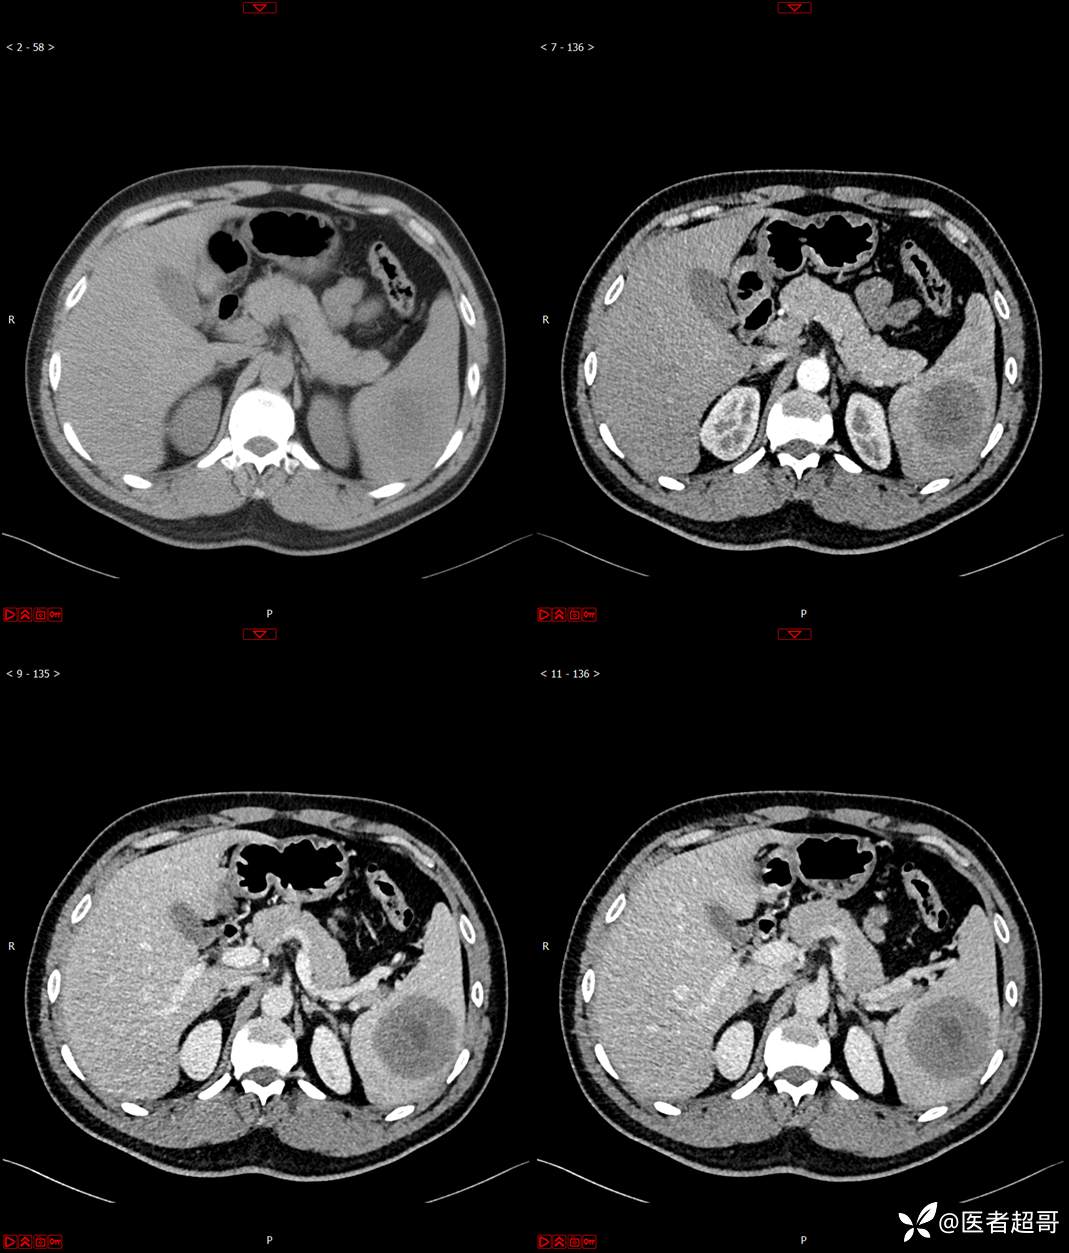

【影诊笔记596】脾脏占位01,你的病谱能网住吗?请分析,留言查询病理及术程!

主 诉:发现脾占位2月余。

现病史:患者2月余前体检彩超提示脾占位性病变,未予特殊诊治,2023.12.1于潍坊市坊子区人民医院行肝胆胰脾MR平扫提示脾脏占位性病变,左肾小囊肿,现患者无腹胀、腹泻,无恶心呕吐,无胸闷憋气等症状,今为求进一步治疗,患者来我院就诊,门诊以“脾占位性病变”收入院。患者自发病以来,一般情况可,神志清,精神可,饮食、二便正常,睡眠可,体重体力无明显改变。